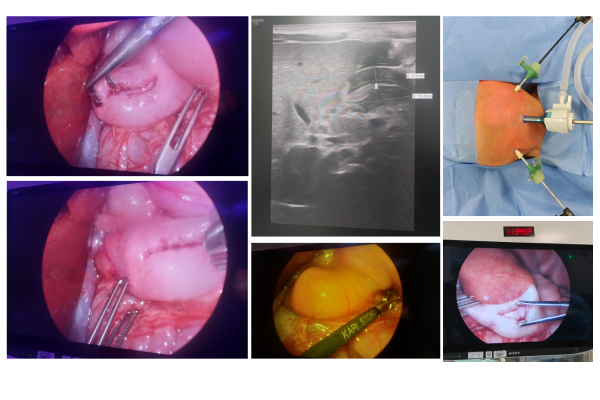

6 year old girl underwent mini-laparoscopic pyeloplasty with 3mm instruments thereby rendering stitch-less abdomimal access. The child had been suffering from frequent intermittent severe pain in left flank associated with vomiting thereby reducing her appetite and general growth. Upon evaluation, she was diagnosed to have severe pelvi-ureteric junction obstruction with enlarged renal pelvis and thinning of left kidney. The child recovered very fast accepting oral feeds and started to move around within 6 hours of surgery. The post- operative pain and discomfort were minimal compared to open surgical repair. The cosmetic outcome, which is one of the major concerns with the child and parents has been outstanding.

There is no scar on her abdomen or perineum which is a great cosmetic benefit to the girl child.